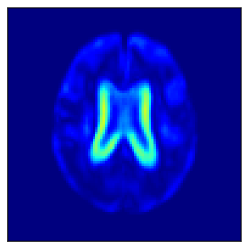

Fig. 5 shows the difference in the reconstructed images (the coronal, sagittal, transverse planes) with and without perturbation to one dimension of the low-dimensional representations that most affect the disease features between AD and CN. This one dimension is chosen to have the largest expected value of the difference in the mean vector ( dim) between AD and CN.

In Fig. 5, the influence of dimensions that may contribute to the diagnosis of AD is examined, and it can be seen that the naïve -VAE captures not only the important areas around the ventricles shown in Fig. 2 but also the edges of the brain and other areas. Loc-VAE, however, is more limited and captures this region better. This result shows that Loc-VAE acquires a specific dimension of the disease features on low-dimensional representation. Disease feature–specific dimensions serve as materials for the neurologist to assess similar cases displayed by CBIR.